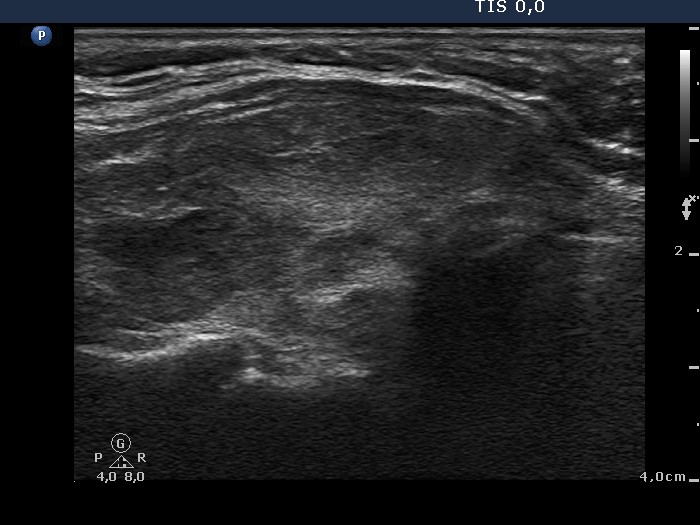

Follow-up examination 12 months later (second row):

Clinical presentation: The patient did not undergo radioiodine therapy. She was well and euthyroid on thyrostatic therapy in the previous year.

Palpation: Both thyroids were enlarged and moderately firm.

Result of blood test: subclinical hyperthyroidism on daily 10 mg methimazole (TSH undetectable, FT4 13.4 pM/L, FT3 5.05 pM/L).

Ultrasonography: The extent of hypoechogenic areas have decreased, otherwise the pattern was unchanged.We suggested again a repeat radioiodine therapy.